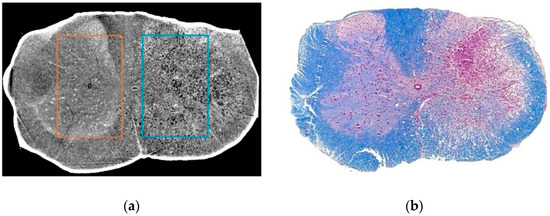

- Fratini, M.; Bukreeva, I.; Campi, G.; Brun, F.; Tromba, G.; Modregger, P.; Bucci, D.; Battaglia, G.; Spanò, R.; Mastrogiacomo, M.; et al. Simultaneous submicrometric 3D imaging of the micro-vascular network and the neuronal system in a mouse spinal cord. Sci. Rep. 2015, 5, 8514. [Google Scholar] [CrossRef] [PubMed]

- Cedola, A.; Bravin, A.; Bukreeva, I.; Fratini, M.; Pacureanu, A.; Mittone, A.; Massimi, L.; Cloetens, P.; Coan, P.; Campi, G.; et al. X-Ray Phase Contrast Tomography Reveals Early Vascular Alterations and Neuronal Loss in a Multiple Sclerosis Model. Sci. Rep. 2017, 7, 5890. [Google Scholar] [CrossRef]